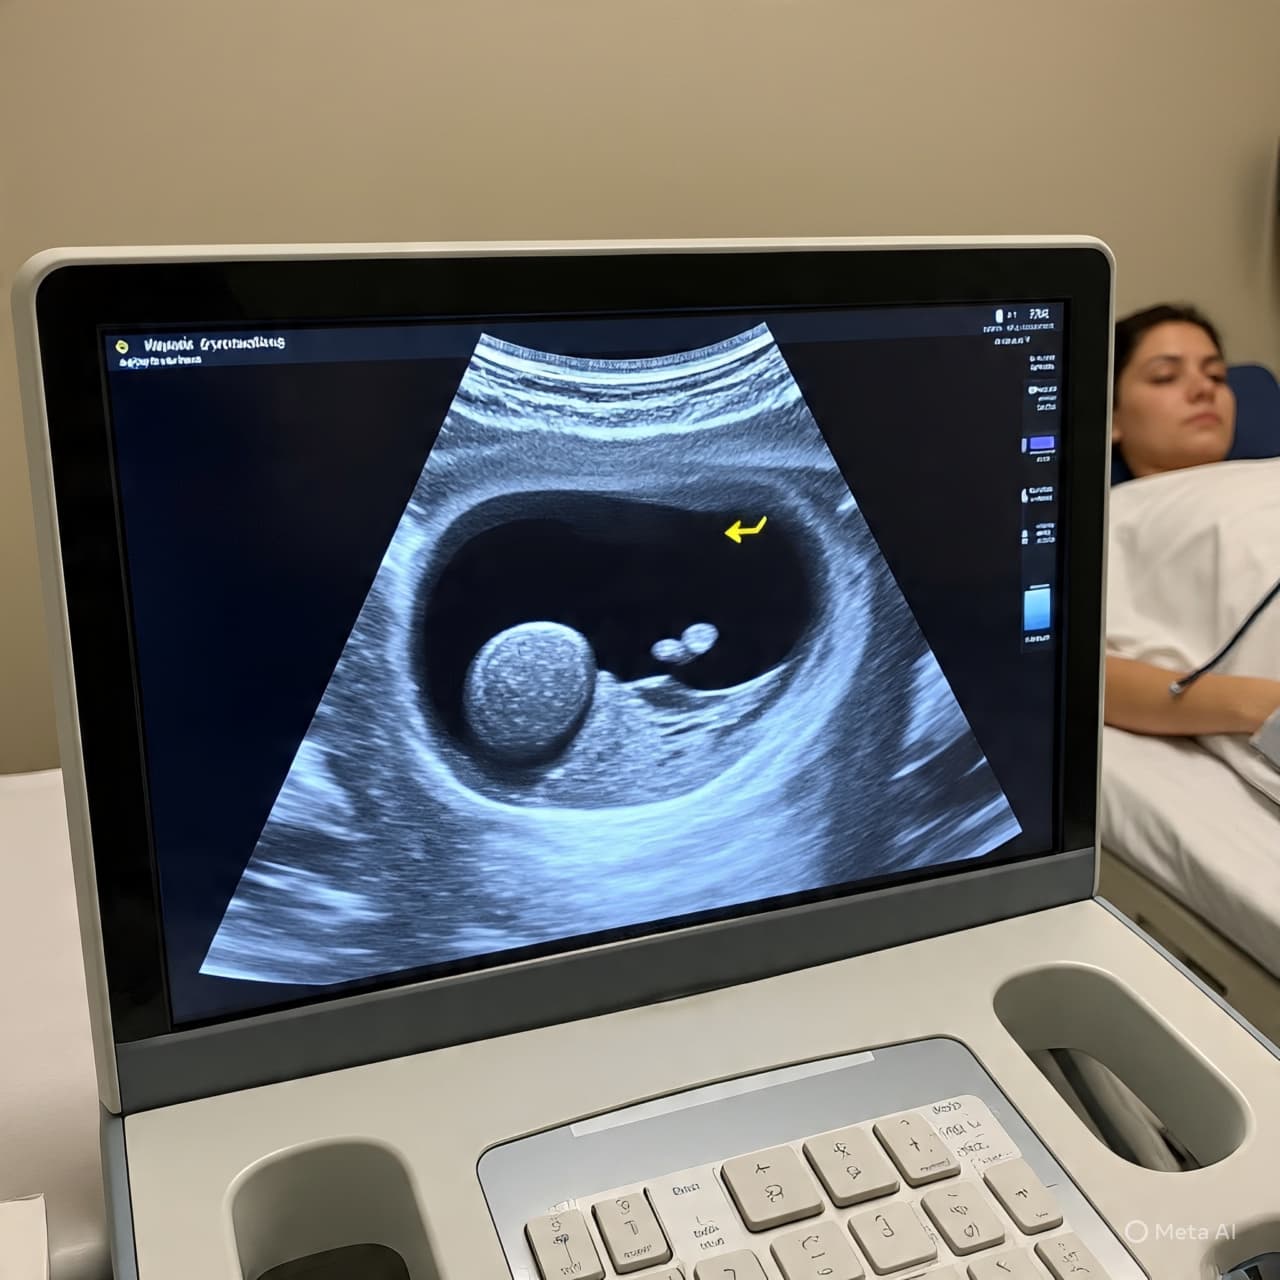

Over the past few decades, health researchers have observed that the number of people diagnosed with thyroid cancer, particularly papillary thyroid carcinoma (PTC), has risen sharply. In the United States alone, the incidence of thyroid cancer has increased by about 250% since 1990, a trend largely attributed to the widespread use of imaging like ultrasonography. Yet this rise has not been matched by a corresponding drop in mortality, suggesting that many of these diagnosed cases would never have posed harm if left undiscovered.

The pattern of overdiagnosis is especially pronounced among women, who show slightly higher percentages within that range, reflecting both biological factors and diagnostic patterns. A legacy of accessible imaging tools, coupled with the tendency to investigate thyroid nodules detected incidentally during unrelated scans, has magnified the number of diagnoses without clear evidence that those extra detections improve survival.

The nuance here is that not all thyroid cancers are the same: some do progress and require treatment. But the challenge lies in distinguishing the small, indolent tumors that may never affect a person’s health from those that will grow and spread. In the current landscape, greater use of imaging and lowered thresholds for investigation have made the former far more visible — a kind of medical abundance that comes with its own costs.

AI Image Disclaimer (Rotated) Images in this article are AI‑generated illustrations, meant for concept only.